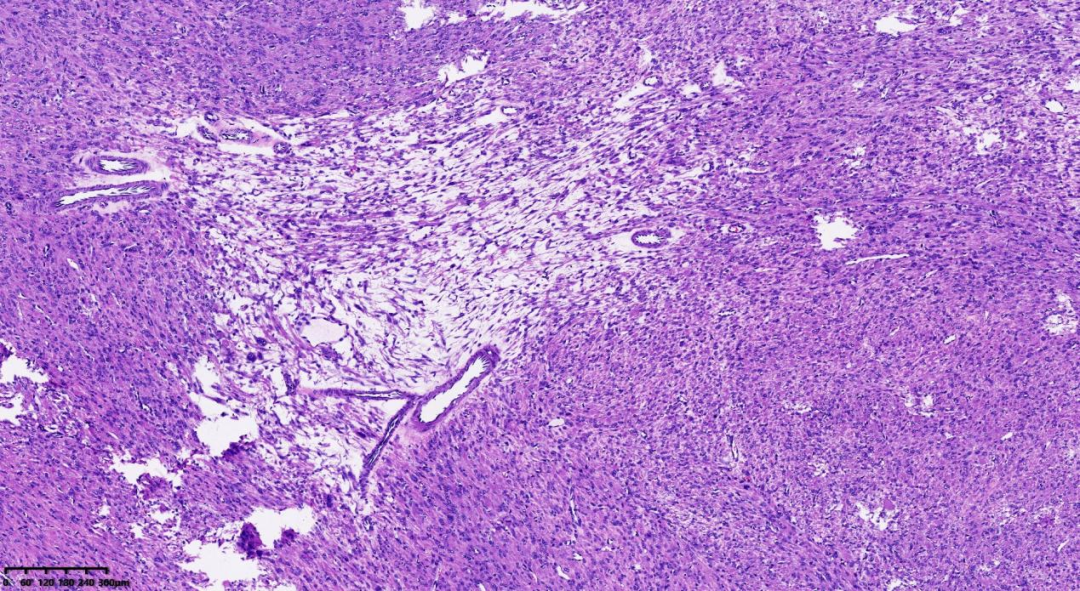

肿瘤细胞密度相对较高,肿瘤间质出现鹿角样血管

肺泡样水肿结构

镜下特征:

肿瘤细胞密度相对较高;间质内常出现鹿角样血管;由于间质常伴有水肿,故形成肺泡样水肿结构;散在分布奇异型细胞及多核细胞;细胞核呈卵圆形;细胞核有时出现链状排列;可见胞质内嗜酸性小体;细胞核中可见突出的嗜酸性核仁,且核仁周围可见空晕。

常为轻度的核不典型性,核分裂象<5/10HPF。